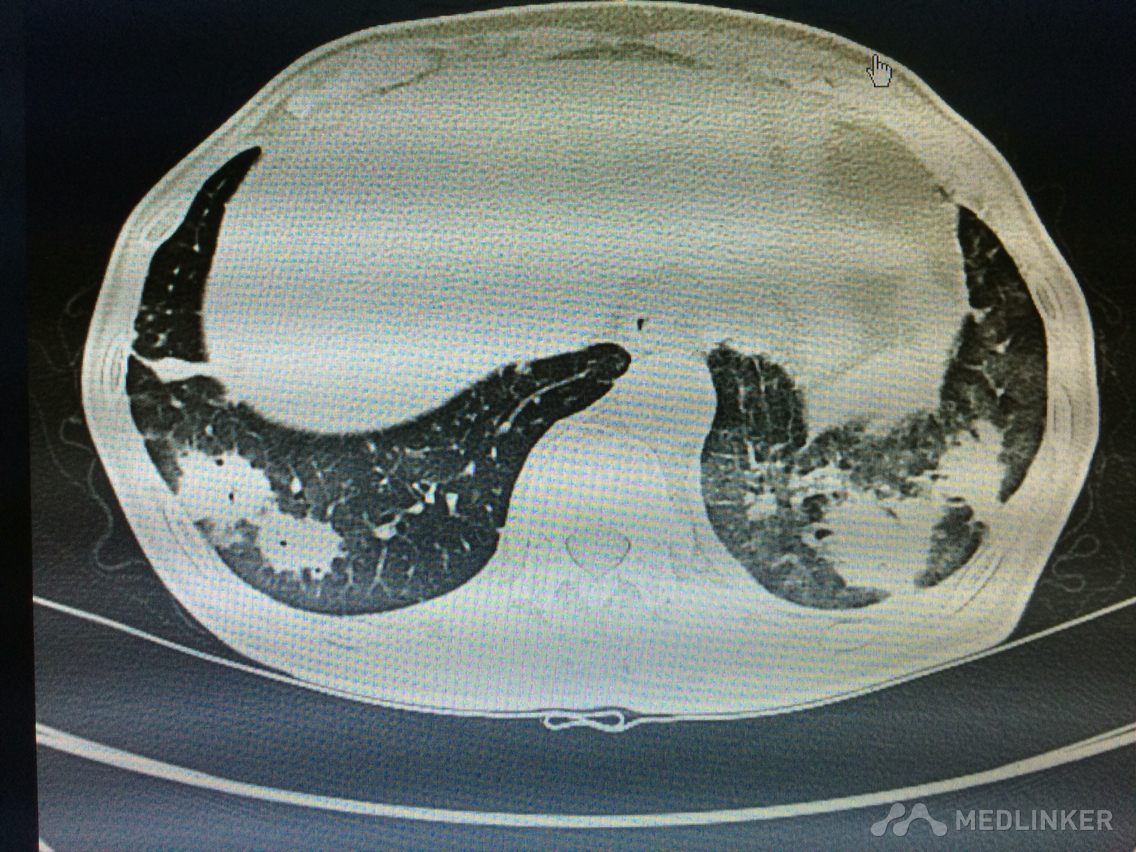

看这胸部CT?

咳嗽咳痰发热3天,伴胸痛气紧,偶痰中带血,体温38.7,伴全身乏力。

胸部!CT,,考虑什么?